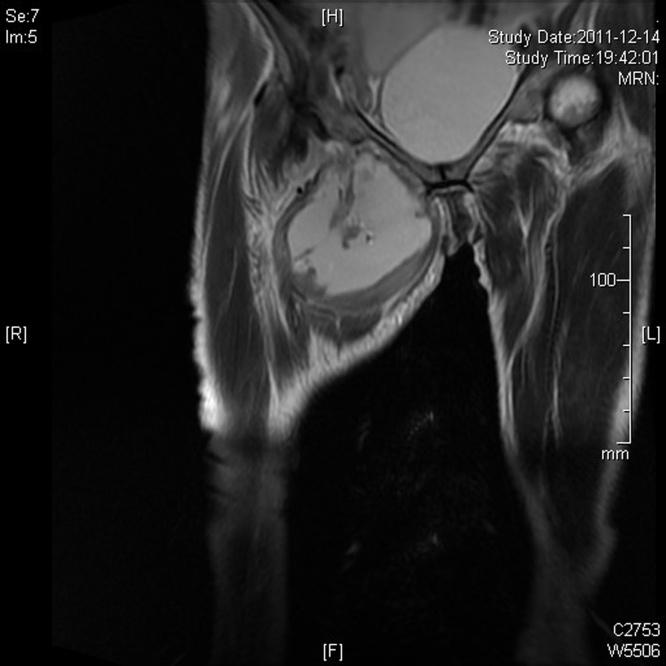

The purpose of this case is to investigate a case of obturator hernia leading to right thigh abscess on 68-year-old woman of China. A 68-year-old Chinese woman was referred to China-Japan Friendship Hospital of Jilin University with abdominal pain, bloating, exhaust, stop defecation in 2011. She had chronic bronchitis, emphysema with a history of 20 years. This patient did not have any bad habits, such as smoking, alcohol consumption, etc. In this surgery, CT was used to diagnose the basic condition of the patient. Surgery was used for treatment of patients with diseases. In addition, this operation was performed by the china-Japan Friendship Hospital of Jilin University. The results of this case showed that the cervix of rectal right anterior wall can hit a funicular neoplasm, toughening, smooth, with tenderness, considering for the external pressure bowel loops. The inside of the right thigh showed obvious swelling, skin slightly bruising, and tenderness. Chest radiographs showed that patients had emphysema, multiple planes of fluid and air in the abdomen. Patients had been successfully operated, but she died because of severe infection.

本病例的目的是调查一名68岁中国女性因闭孔疝导致右大腿脓肿的病例。一名68岁的中国女性于2011年因腹痛、腹胀、排气、停止排便被转诊至吉林大学中日联谊医院。她有20年慢性支气管炎、肺气肿病史。该患者没有吸烟、饮酒等任何不良习惯。在此次手术中,使用CT诊断患者的基本病情。采用手术治疗该患者的疾病。此外,此次手术由吉林大学中日联谊医院实施。该病例结果显示,直肠右前壁宫颈可触及条索状肿物,质韧,表面光滑,有压痛,考虑为肠管外压。右大腿内侧明显肿胀,皮肤轻度瘀斑,有压痛。胸部X线片显示患者有肺气肿,腹部有多个气液平面。患者手术成功,但因严重感染死亡。